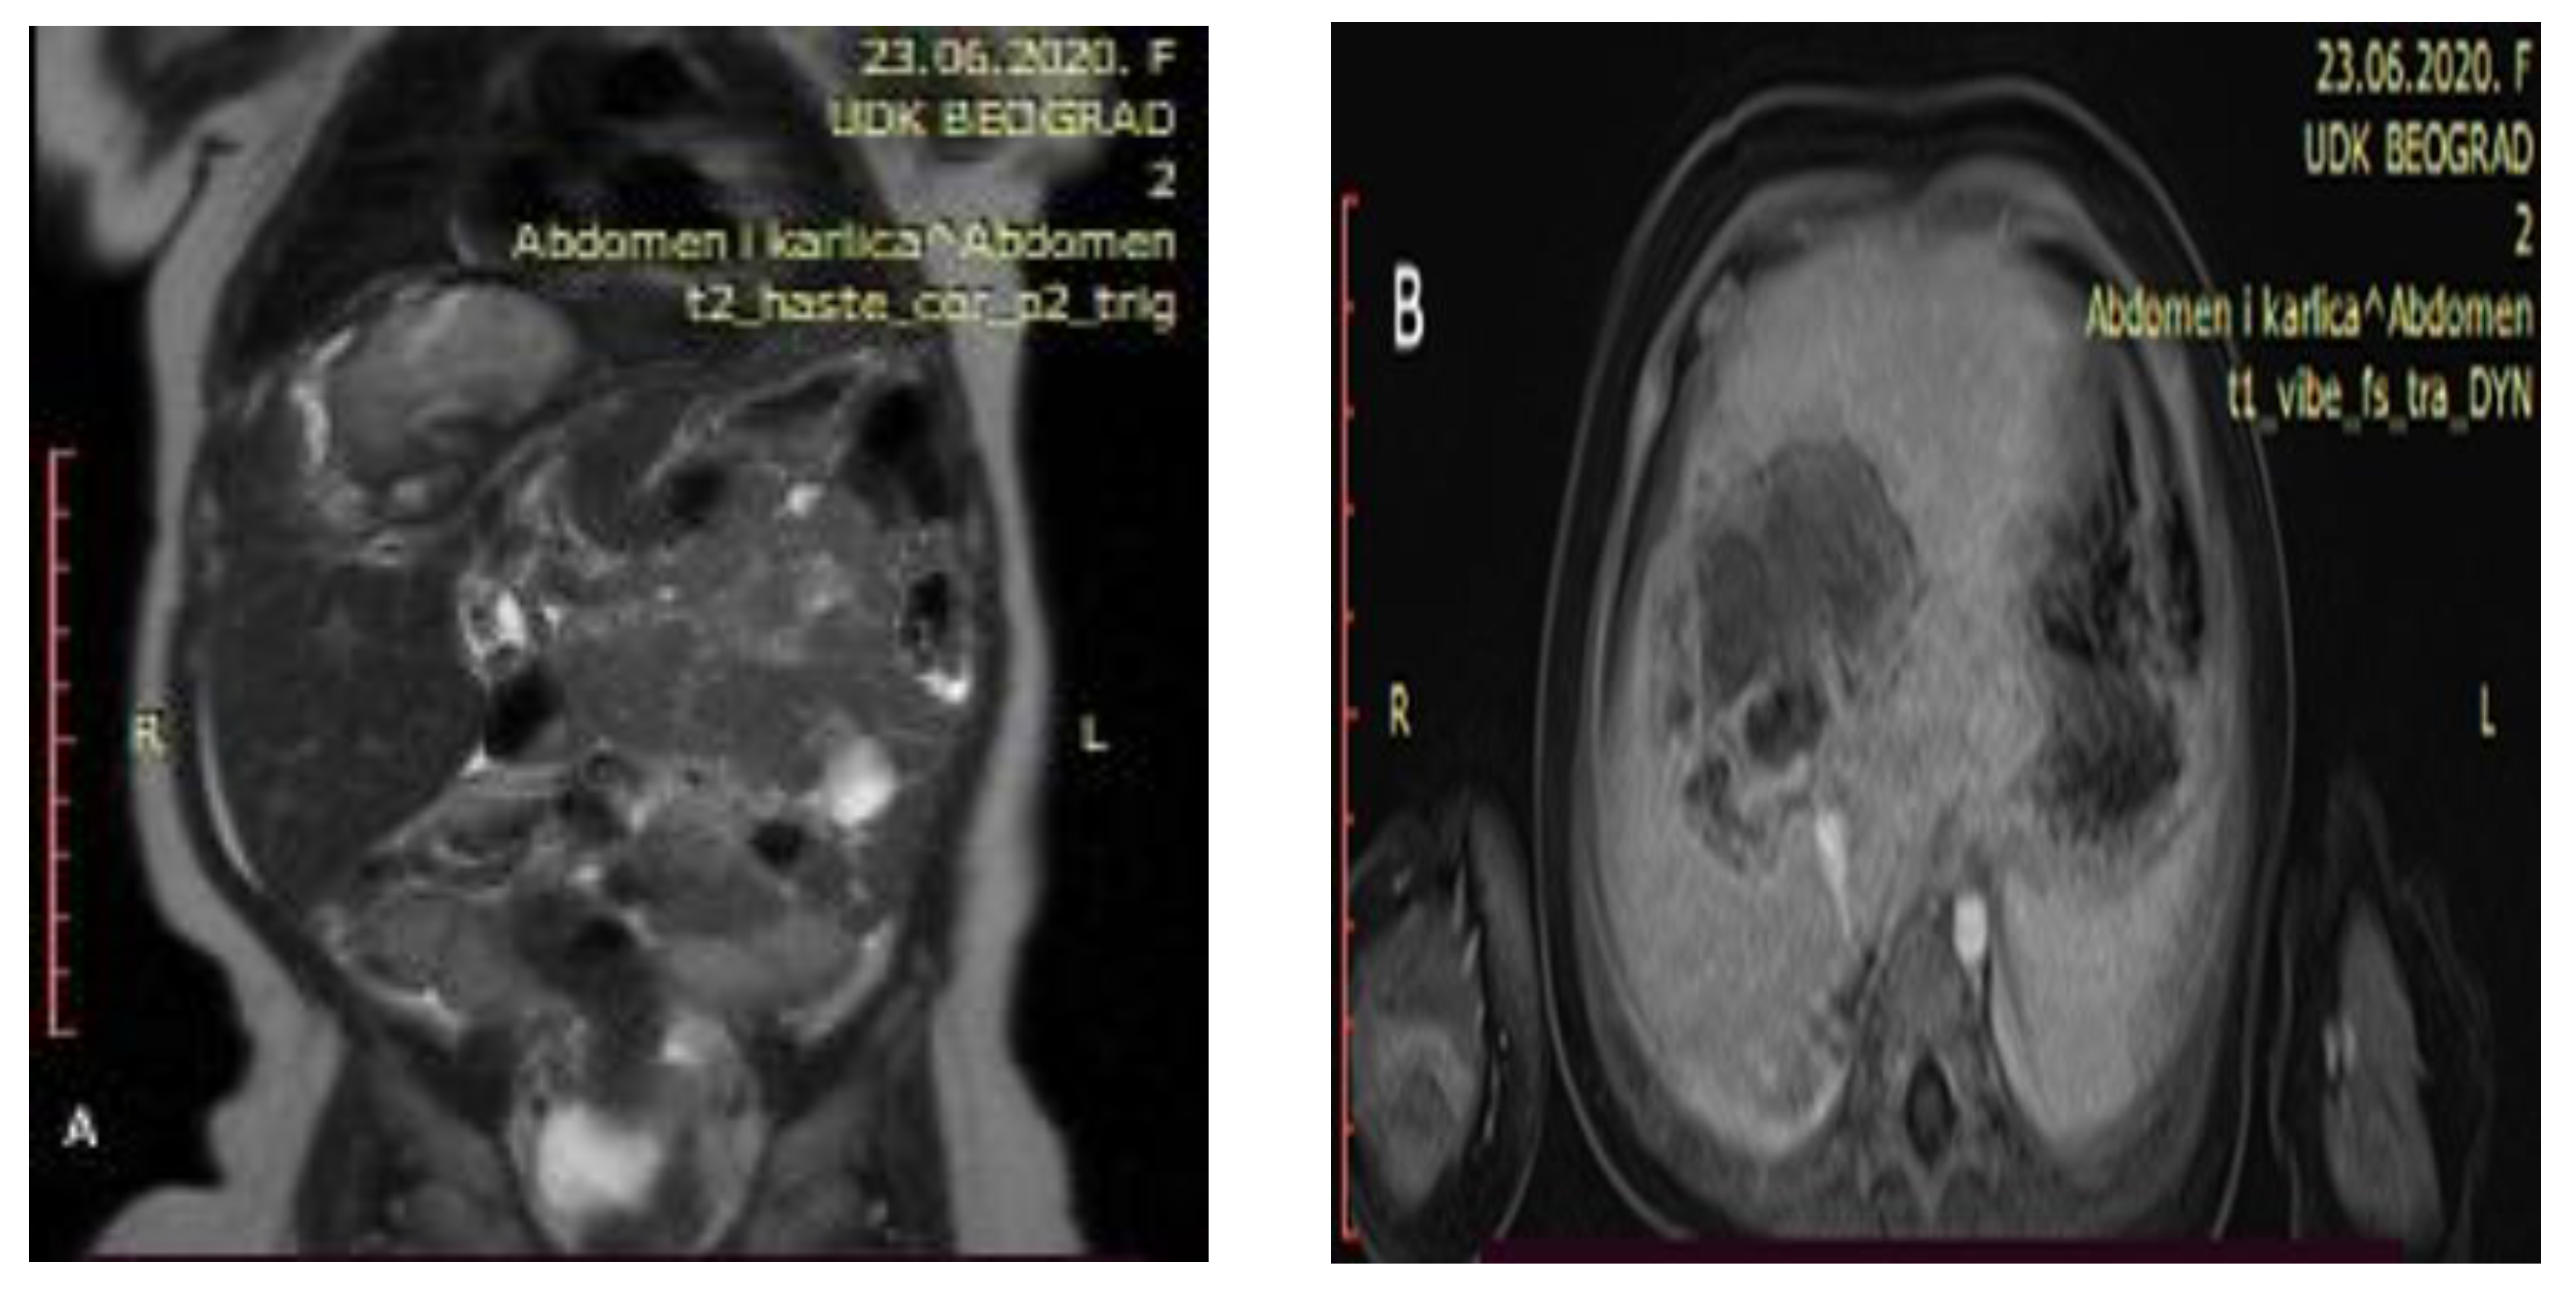

Control abdominal MRI showed a significant decrease in the initial tumor mass (62 mm × 47 mm × 45 mm) with mostly cystic and necrotic morphology (Figure 3). The right hepatic vein was intact, the intermediary hepatic vein went straight through the tumor, and the left hepatic vein encircled the tumor next to its border. Both portal vein branches were intact as well as the inferior vena cava and hepatic arteries.

Figure 3.

Control abdominal MRI after six cycles of chemotherapy showing a significant decrease in the tumor mass ((A) showing the coronal plane view of the MRI; (B) showing the axial plane view of the MRI).